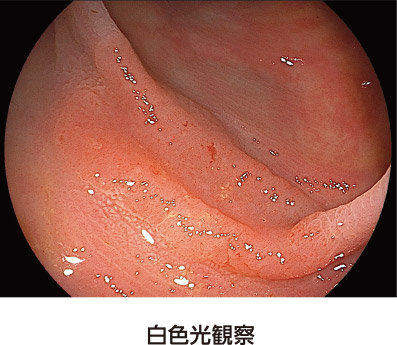

通常の観察画像です。